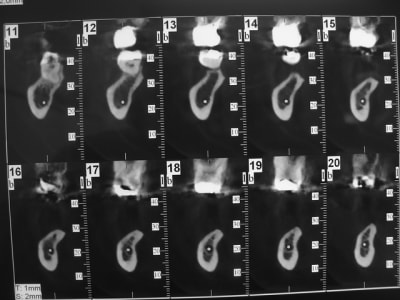

Patiente agée d'une trentaine d'année. En bouche la crête osseuse est inapparente et absence de gencive attachée.

Dans les secteur d'emmergence du nerf mandibulaire la palpation est douloureuse.

coupe_secteur_3_akuiru.jpg

coupe_sect_4_c0hkw3.jpg

sinon secteur 3 y a peut être moyen dans certaines zones de travailler avec l'expansion...mais pas facile comme cas...surtout si la demande esthétique est +++

Effectivement, dans la mesure ou on ne doit gagner qu'en largeur, je ferais une régénération en utilisant des vis en tuteur et du puros.

1. 2 séances d ostéotension

2. Epaississement vestibulaire en zone molaire nanobone prfd jason

3. pose de 2 cylindres enfouis en 34 44

4. pose de monodisk en 36 37 46 47 enfouis bloqués par vis ostéosynthèse

Mouais! Mais elle veut la hauteur en plus.

Justement c'est la laxité du lambeau qui m'inquiète +++++